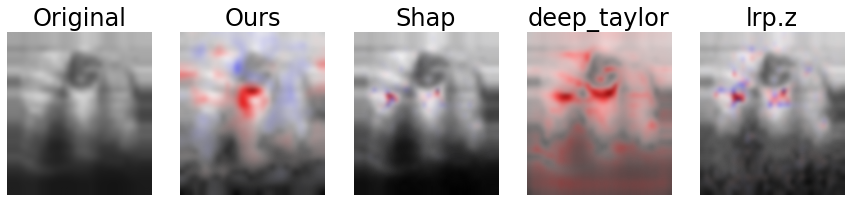

The results of the user study are listed in Tables 3 through 6 and visualized exemplarily for the LIDC-IDRI data set in Fig. 11. A qualitative comparison of our approach to DeepSHAP, DeepTaylor and LRP is depicted in Fig. 8.

Regarding the tested criteria, our method outperformed all other tested methods on the LIDC-IDRI dataset with average raw values of 1.92, 95 % CI [0.50, 3.13], 1.76 [0.25, 3.13], and 1.04 [-0.63, 2.50] for intuitive validity, semantic meaningfulness and image quality, respectively. Average values for the second best method for each criterion were -1.52 (DeepTaylor, , two-tailed -test), -1.54 (DeepSHAP, ), and -.85 (DeepTaylor, ). Regarding intuitive validity and semantic meaningfulness, our method was significantly superior to all other tested methods with . Regarding image quality, significant superiority could be shown to DeepSHAP and LRP (, while for DeepTaylor the result was non-significant with .

The z-adjusted values of our method were 2.84, 95 % CI [1.50,3.98], 2.78 [1.39,4.10] and 2.04 [0.50,3.41] for intuitive validity, semantic meaningfulness and image quality. Significant superiority could be shown analogously to the unadjusted values to each method and each criterion with -values between with the exception of image quality from the DeepTaylor algorithm ().

The average rank of our method in direct comparison was 1.28, 1.36 and 1.52, for intuitive validity, semantic meaningfulness and image quality, compared with 2.78, 2.71, 3.23 (DeepSHAP/DeepTaylor/LRP) for intuitive validity, 2.75, 2.75, 3.41 for semantic meaningfulness and 3.04, 2.36, 3.07 for image quality. ranged from , again with the exception of image quality for the DeepTaylor algorithm ().